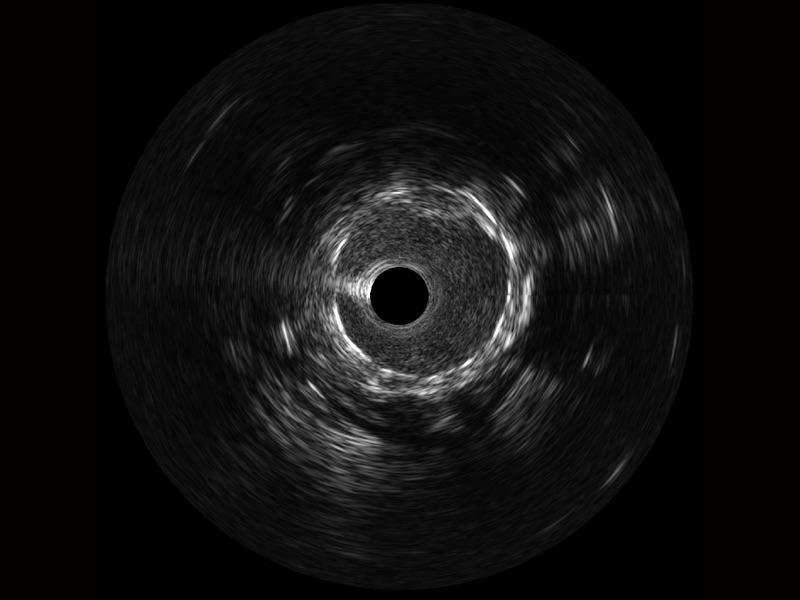

传统IVUS图像

对比传统IVUS导管成像,诸侯快讯官网宽频IVUS图像的近场支架梁显影更细腻,远场中膜外血管仍清晰可辨,兼顾远中近,兼顾分辨力与穿透深度